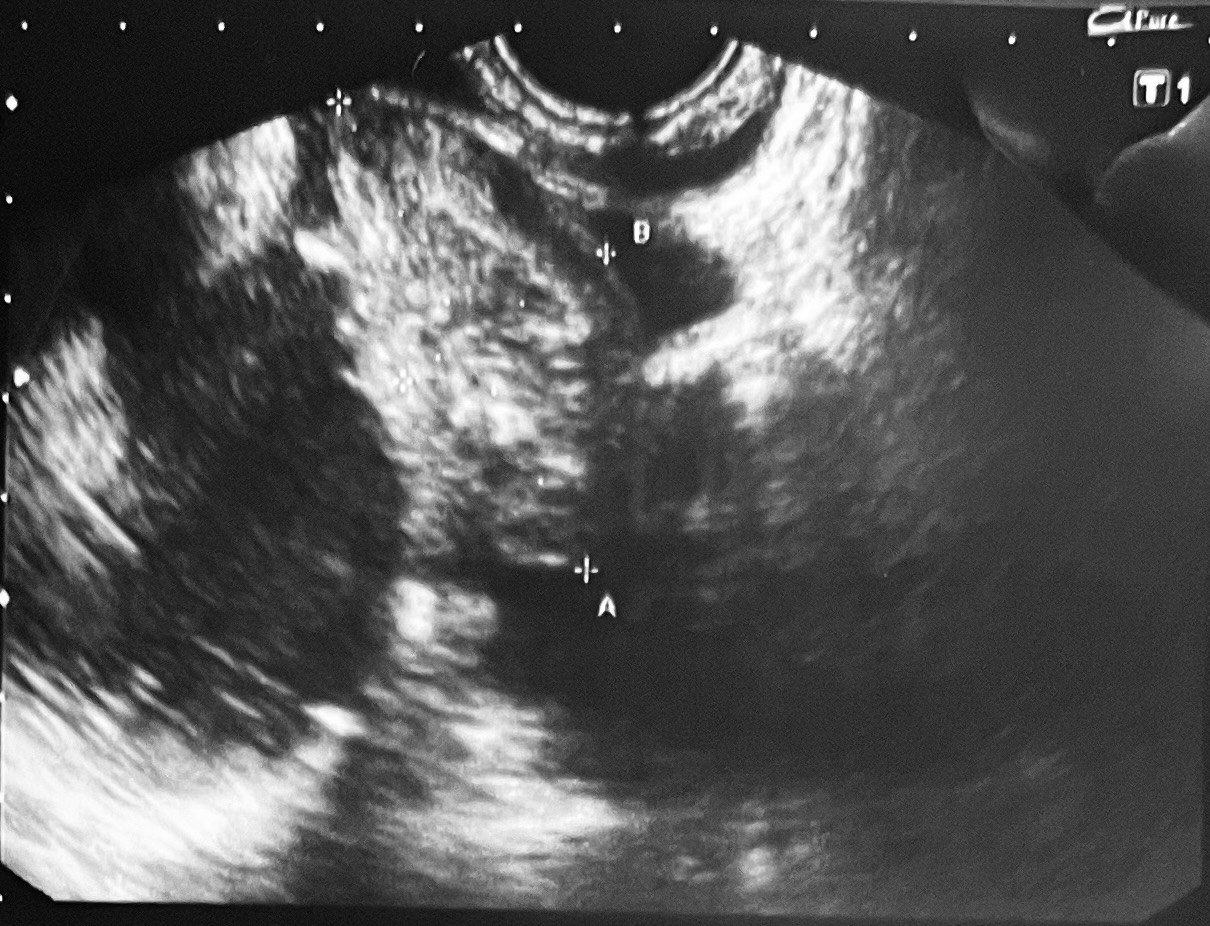

La ecografía clínica abdominal identificó una masa anexial heterogénea con áreas hiperecogénicas y refringentes, además de moderado líquido libre pélvico, hallazgos compatibles con lesión compleja de probable origen teratomatoso.

Ante estos datos se realizó interconsulta urgente a Ginecología, que mediante ecografía transvaginal confirmó múltiples imágenes anexiales heterogéneas con componentes sólidos y líquidos y focos hiperrefringentes sugestivos de teratoma dermoide.